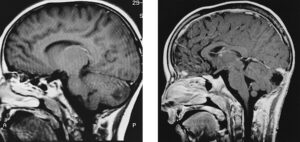

Ha due anni e uno sviluppo emotivo, comportamentale e sociale nella norma. Eppure presenta una grande cisti porencefalica nell'emisfero sinistro,...